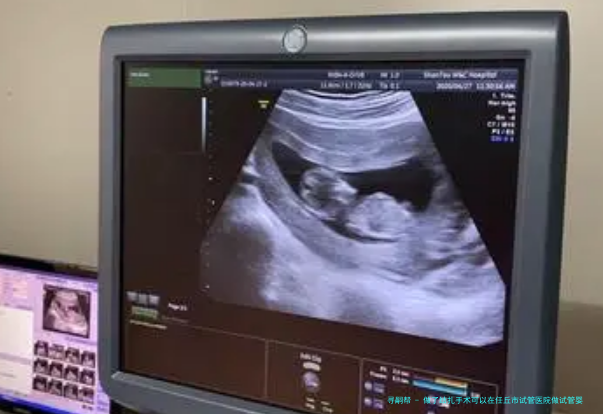

绝育手术是通过割断或封闭输卵管或输精管的方式,制止精子与卵子相逢,从进而达到到节育的成果。关于已然进行告终扎手术但又希望生育的夫妇来说,试管婴儿是1个可行的选择。在试管婴儿过程中,医生会先使用药物刺激女性卵巢出现多个卵子,然后通过微创手术拿出卵子,在试验室环境中与男方提供的精子结合,形成胚胎。其后,抉择最优质的胚胎移植到女方子宫内,以此期望成功着床并发育成胎儿。